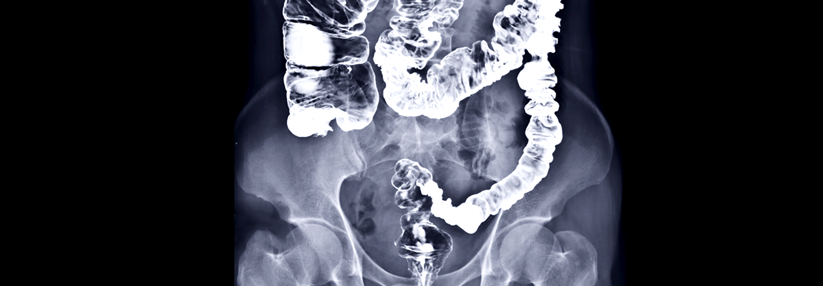

In Tierversuchen fanden sich bereits Anhaltspunkte für tumorlastförderne Effekte einer Eisenergänzung bei Darmkrebs. Forscher um Dr. Nathalie M. Scheers von der Chalmers University of Technology in Göteborg unterstützen diese Beobachtung nun anhand von In-vitro-Versuchen mit Fe-Chelatverbindungen an zwei Typen humaner Kolonkarzinomzellen.

Die Experten setzten dabei Dosierungen ein, die den Eisenspiegeln im Darmtrakt bei einer normalen Supplementierung entsprechen. Es stellte sich heraus, dass Eisencitrat und Eisen-EDTA die Produktion von Amphiregulin – einem löslichen parakrin wirkenden Wachstumsfaktor – und dessen Rezeptor fördern. Das Protein gilt als bekannter Krebs-Biomarker. Eisensulfat hingegen zeigte keinen solchen Effekt.

Folglich dürfte nicht das Eisen per se für erhöhte Amphiregulinlevel verantwortlich sein, so die Autoren. Vielmehr vermuten sie einen Einfluss des dreiwertigen Eisens in Chelatverbindungen auf den entzündungsassoziierten COX*-2-Signalweg, der seinerseits beim Kolonkarzinom eine Rolle zu spielen scheint.

Die Ergebnisse geben Anlass zur Vorsicht, meint Dr. Scheers in einer begleitenden Pressemitteilung der Chalmers University of Technology. Zumal Komplexe mit Citrat und EDTA weltweit als Nahrungsmittelzusatz bzw. als Supplemente eingesetzt werden und im Alltag kaum zwischen den Eisenpräparaten unterschieden wird.

Empfehlungen zur „richtigen“ Ergänzung gibt die Expertin nicht. Außerdem räumt sie ein, dass es sich um eine In-vitro-Studie handelt. „Die Leute sollten sich also weiterhin nach den offiziellen Empfehlungen richten.“ Nach ihrer persönlichen Meinung gefragt, würde sie Eisencitrat künftig aber eher meiden.